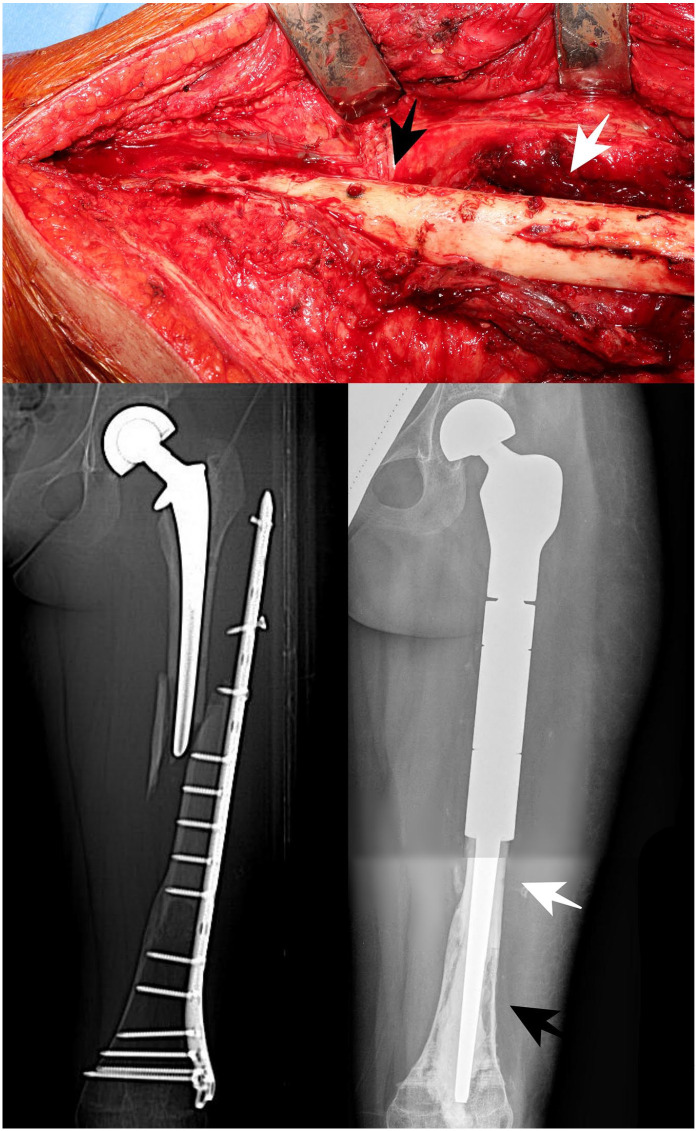

Methods: We reviewed 10 pediatric patients treated with proximal femur resection for a primary bone tumor and reconstruction with short stem allograft-prosthesis composite, with at least 24 months follow-up. The median age was 9 years (4-13) at surgery. The mean resection length was 15 cm (6-29). In six cases, fixation was performed with a short plate positioned under the great trochanter while in four cases a long plate extended over the great trochanter was employed.

Results: Nine complications that required surgical revision were assessed in six patients (one wound dehiscence, two nonunions, two fractures, one acetabular wear, three hypometria), while allograft-prosthesis composite removal was required in three patients. The revision-free survival was 57% (95% confidence interval 33%-100%) at 5 and 10 years. The graft removal-free survival was 75% (95% confidence interval 50%-100%) at 5 and 10 years. The mean Musculo-Skeletal Tumor Society Score was 28 (20-30).

Conclusions: Allograft-prosthesis composites with short stem and compression plate represents an effective reconstructive option after proximal femur resection for primary bone tumors in growing patients, preserving bone stock. The use of a compression plate extended over the greater trochanter seemed to reduce failure rate.